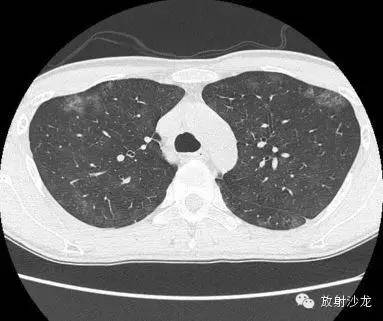

首次就诊CT:

胸片示两肺中下野边界不清的磨玻璃样阴影(GGO)。CT示两肺地图样分布的GGO,主要位于两肺上叶、右肺中叶及两肺下叶,其中两肺下叶多发的GGO融合并伴有小叶间隔增厚。2周后随访胸片示双肺野弥漫分布的GGO增多。患者第一次就诊时未告知自己的性取向。只告知了曾接触过染发剂。患者按肺间质性疾病给予激素治疗。然而,治疗后患者的症状和影像学表现均加重。患者血液检测结果显示艾滋病病毒阳性。支气管肺泡灌洗液GMS染色示大量的卡氏肺孢子虫。